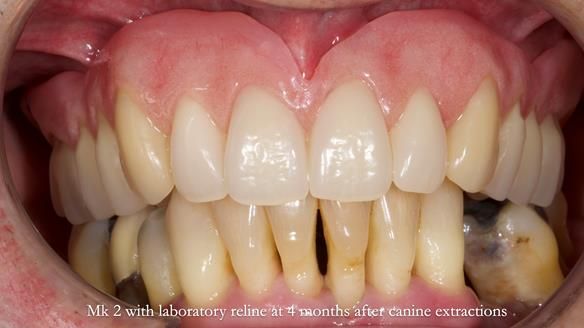

Twelve months after the final extractions, I made the Mk3 definitive complete upper denture.

Three months after fitting, a reline was carried out to adapt to tissue changes from the canine and molar extractions.

For the Mk3, we embedded the metal base fully within the fitting surface acrylic. This design allowed adjustment of the polished surface using universal marking spray to fine-tune sibilance and prevented any join between the metal and acrylic from being felt by the tongue.

This approach solved most (but not all) of the speech issues.